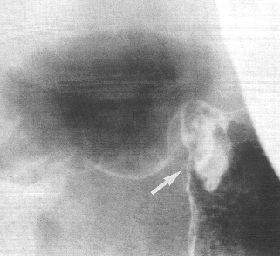

Case 33.9 A.F., 66 year old male. Radiology: 2.5 cm mass lesion partially obstructing pyloric aperture. Base of gas-filled duodenal bulb normal (Fig. 33.9). Operation: small ulcerated pyloric mass causing partial obstruction. Serosal spread and lymph node metastases. Spread into proximal 2.0 cm of duodenum. Billroth II. Gastric histology: well differentiated adenocarcinoma, intestinal type. Duodenal histology: spread into submucosa for 2.0 mm and into mucosa for 1.0 mm.

![]() |

| Fig. 33.9. Case A.F. Small mass lesion at pyloric aperture (arrow). Base of gas-filled duodenal bulb normal. |